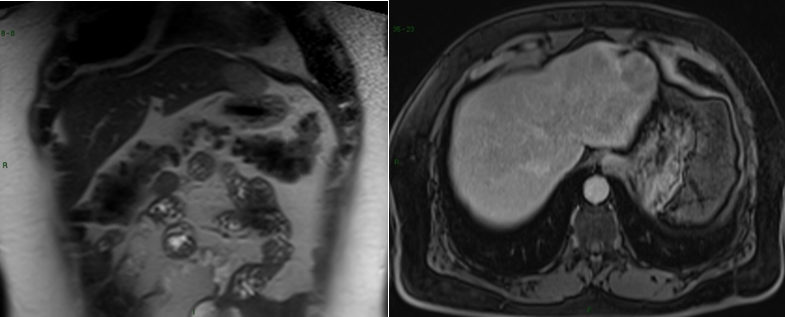

Male, 47 years old, with an incidental finding of hepatic lesion, during investigation of nephrolithiasis. Previous history of splenectomy after abdominal trauma due to automobile accident 20 years ago. Hypertensive in use Olmesartan, denied other pathologies and surgeries. On physical examination: good general condition, anicteric, painless abdomen, without palpable masses. Laboratory tests: Hb 14g/dL (13,5 - 17,5), Hct 44,4% (39 - 55), Platelets 268,000/mm3 (150.000 - 400.000), creatine 0,9mg/dL (1,5), INR 0,8, CEA 1,33 ng/mL (<3,0), CA 19-9 20U/mL (<37), AFP 1,5ng/dl (<7,22 ), albumin 4,19g/dL (3,4 – 4,8), AST 20U/L (17 - 55), ALT 18U/L (21-71), GGT 54U/L (15/73), AP 48U/L (38 - 126), total bilirrubin 0,57mg/dL (0,2 – 1,3). MRI showed nodular hepatic lesion, 42x41x28mm, slight hyperintense in T2, with contrast enhancement and washout in late phase, in segment II, without dilatation of biliary tract (Figures 2). The initial diagnosis was hepatic adenoma. Proceeded with hepatic segmentectomy, with good evolution. The surgical specimen referred to pathological anatomy and revealed hepatic splenosis (Figures 1).

Intrahepatic splenosis shows increased enhancement on CT or MR images during the arterial phase. Performing gadoxetic acid–enhanced hepatocyte-phase MR imaging does not help because intrahepatic splenosis is hypointense during the hepatospecific phase. The MR technique involving administration of small iron oxide particles (SPIO-Endorem), which is taken up by liver and spleen reticuloendothelial cells, has proven to be effective in differentiating intra-hepatic splenosis from other lesions.14,15,18 With SPIO (superparamagnetic iron oxide) intrahepatic splenic nodes remain hyperintense.19 Noncontrast CT reveals a well circumscribed iso- or hypodense mass in the liver, while noncontrast MRI demonstrates mild-to-moderate hyperintensity on T2-weighted image and hypointensity on the T1-weighted image. A dynamic study on CT and MRI shows a slight to intense enhancement, which may be homogeneous or heterogeneous during the arterial phase but enhancement is diversely during the portal venous and equilibrium phases in different cases. Compared with the surrounding hepatic parenchyma, the lesion could reveal hypodensity and hypointensity, or hyperdensity in the arterial phase. Or it can demonstrate diminished enhancement, slight enhancement, or increased enhancement during the following phases (Figure 2 & 3).19,20

Figure 2 Magnetic Resonance Imaging (MRI). T2-weighted (A and B) and T1-post-contrast (C, D and E) images, in axial (A, C, D and E) and coronal (B) planes, that demonstrate subcapsular nodule in liver segment II, with intermediate sign in T2, enhancement in the post-contrast arterial phase (C) and washout with capsular enhancement in the venous phase (D). Signs of splenectomy and small implants of splenic tissue in the left subphrenic region (E) are also noted.